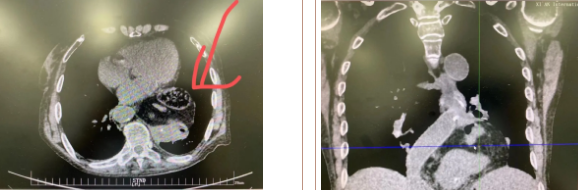

經(jīng)過三周充分準備、院內(nèi)多學科會診及嚴謹?shù)男g(shù)前討論,西安國際醫(yī)學中心醫(yī)院胸科醫(yī)院李文海副院長帶領(lǐng)團隊為一位82歲高齡,多臟器功能不全且合并腫瘤患者成功實施“巨大膈疝修補 抗返流手術(shù)”。

據(jù)了解,患者多年來進食后出現(xiàn)惡心、嘔吐,卻未到醫(yī)院進行檢查。3個月前患者突然出現(xiàn)無尿,全身腫脹等情況才前往就醫(yī),卻遭多家醫(yī)院拒收,輾轉(zhuǎn)來到我院就診。檢查發(fā)現(xiàn)患者已患宮頸癌、進而引起腎后性腎衰、同時合并膈疝、出現(xiàn)泌尿道感染,病情及其復雜。

經(jīng)泌尿外科積極救治,患者腎衰癥狀緩解,隨后轉(zhuǎn)入放射治療中心進行宮頸癌根治性放療。放療期間,患者惡心、嘔吐癥狀逐漸加重,后期無法進食,排除機械性腸梗阻和放療因素,考慮因長期膈疝加重引起,經(jīng)胸外科會診后轉(zhuǎn)入胸外科一病區(qū)準備手術(shù)治療。

麻醉手術(shù)中心副主任丁倩為減輕患者術(shù)后不適,實施單腔聯(lián)合支氣管封堵插管,同時進行了肋間神經(jīng)阻滯麻醉。術(shù)中發(fā)現(xiàn)患者膈疝巨大,食管和疝囊分界不清,部分胃組織和結(jié)腸疝已進入胸腔。李文海憑借豐富的臨床經(jīng)驗,仔細辨別解剖變異,有序完成分離、縫合、修補等一系列操作,胸外科穆強副主任醫(yī)師、劉歡住院醫(yī)師、麻醉手術(shù)中心團隊通力配合,手術(shù)最終順利完成,患者安全返回胸外科監(jiān)護室病房。目前患者術(shù)后恢復良好,于近日準備出院。